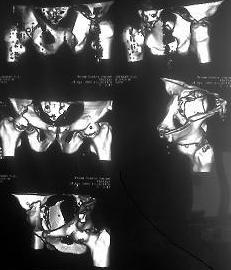

[Ortho] Перелом вертлужных впадин

Имя     : 2.JPG

Имя     : 7.jpg